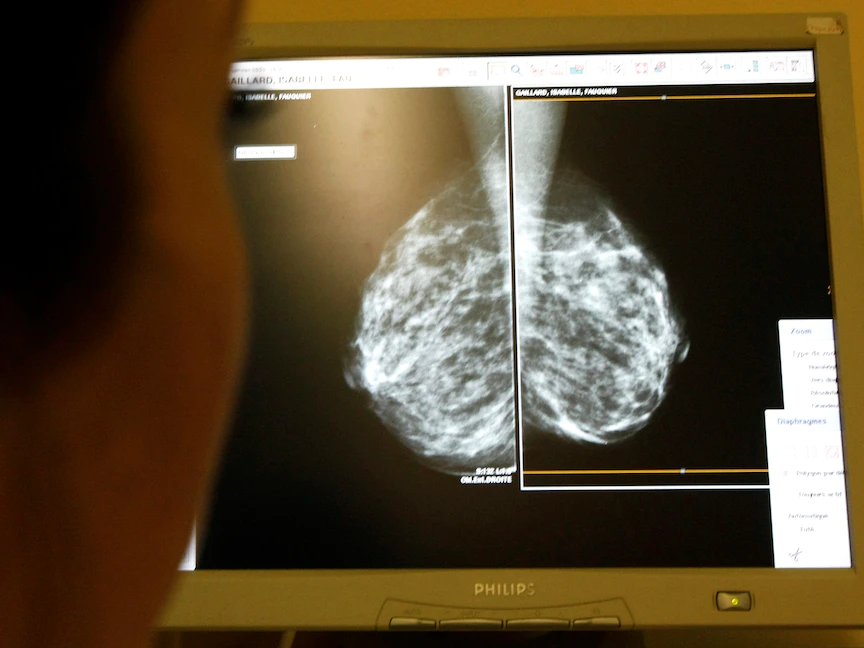

ويأمل الباحثون اختبار تلك الطريقة على سرطانات الثدي المتقدمة.